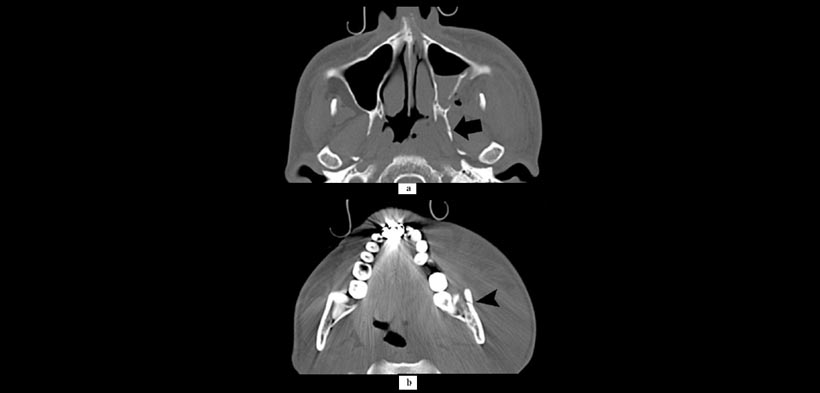

Figura 3. Compromiso de la vía aérea debido a los tejidos inflamados parafaríngeas en un paciente de 36 años de edad. (a) Muestra fractura de la pared del seno maxilar y la placa lateral de la pterigoides (flecha) y (b) muestra fractura en el ángulo mandibular (punta de flecha).